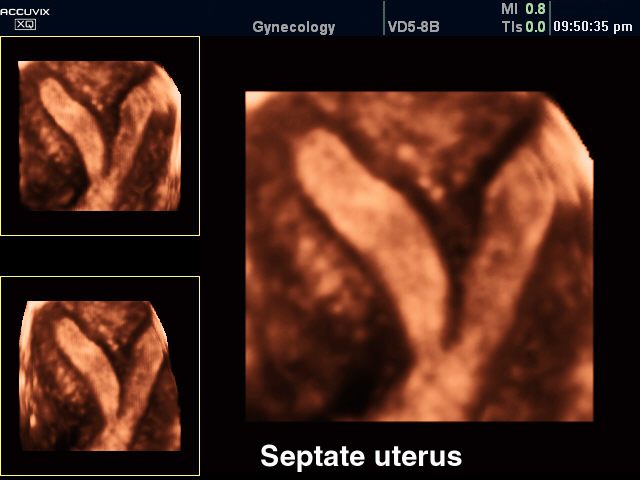

3-хмерное УЗИ при двурогой матке

В диагностике седловидной матки решающая роль отводится инструментальным исследованиям – УЗИ, УЗГСС, гистероскопии, гистеросальпингографии, магнито-резонансной томографии. Стандартное гинекологическое исследование при седловидной матке неинформативно.

В процессе эхографии малого таза (УЗИ) седловидная матка выявляется не всегда. При значительной деформации поперечное сканирование позволяет выявить увеличение ширины дна матки до 68 мм, утолщение миометрия стенки дна до 10-14 мм и его выбухание в полость органа. Для обнаружения седловидной матки УЗИ предпочтительнее проводить влагалищным датчиком во вторую фазу цикла при достаточно выраженной толщине эндометрия.

Наиболее достоверно характерные признаки седловидной матки обнаруживаются при проведении гистеросальпингографии: на рентгенограммах определяются 2 устья фаллопиевых труб, в области дна отчетливо читается небольшое углубление в виде седла, вдающееся в полость матки. Аналогичные признаки выявляются при проведении ЯМРТ. Гистероскопия используется для непосредственного визуального обследования полости матки. В процессе ведения беременности у пациенток с седловидной маткой осуществляется мониторинг допплерографии маточно-плацентарного кровотока, проводится кардиотокография, фонокардиография плода.